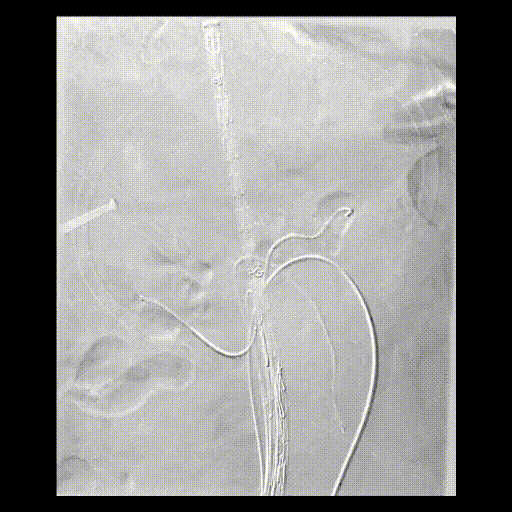

手术方案:内脏区体外三开窗(CA、SMA、LRA),RRA原位开窗。

预三开窗+右肾原位开窗重建

Fustar+Futhrough原位穿刺破膜

预三开窗+肾动脉原位开窗重建